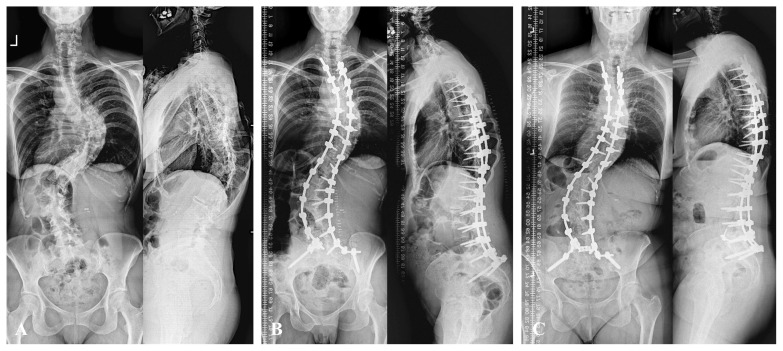

Abstract Image